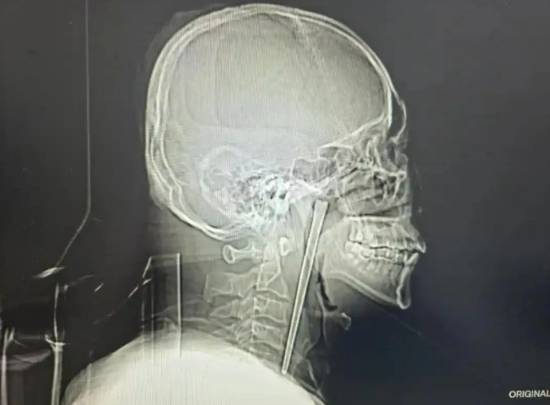

接诊的黄巍鹏医生详细询问病史后,立即为王先生安排电子喉镜检查,结果清晰显示,其右侧咽后壁黏膜下、软腭后侧有一根金属筷子嵌入,肉眼可见部分约3厘米。万幸的是,经细致探查,异物邻近的咽部黏膜未出现明显破溃、出血及化脓情况,声带活动正常,喉腔结构也未受到压迫移位,为后续手术创造了良好条件。